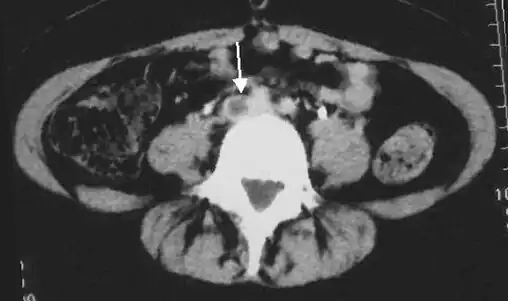

Doppler ultrasonography showing absence of flow and hyperechogenic content in a clotted femoral vein (labeled subsartorial[h]) distal to the branching point of the deep femoral vein. When compared to this clot, clots that instead obstruct the common femoral vein (proximal to this branching point) cause more severe effects due to impacting a significantly larger portion of the leg.[122] - An abdominal CT scan demonstrating an iliofemoral DVT, with the clot in the right common iliac vein of the pelvis

-